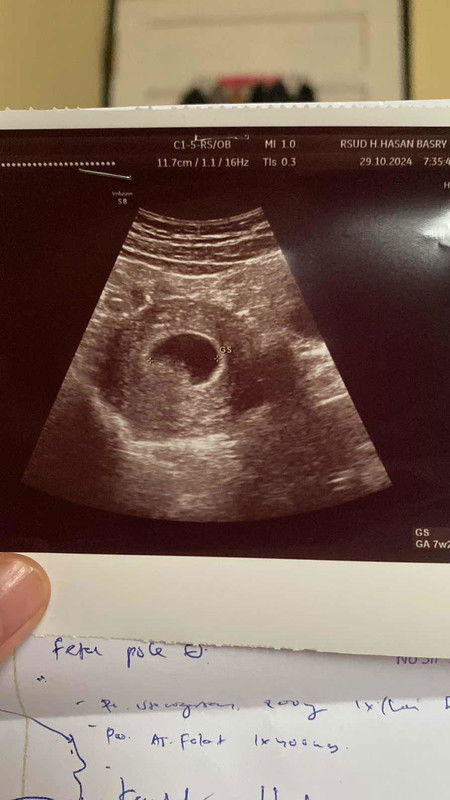

Bun aku mau berbagi pengalaman . Kemarin di usia janin ku 7 minggu . Aku keluar flek 2 hari 🥲. Terus aku usg ke dokter baru ada kantung kehamilan . Sedangkan normalnya katanya harus nya udah ada bakal janin. Al hasil aku di suruh usg 1 bulan lagi. Selama satu bulan itu aku drop banget. Jadi malas makan apapun karna bawaan aku juga gabisa nyium bau bawang. Aku cuman konsumsi asam folat (blackmories) , kalsium, sama d3 , dan susu manis indomilk kids karna cuman susu itu yang menurutku enak😆 . Udah satu bulan kemudian di usia kandungan ku 11 minggu usg lagi dan janin aku udah ada kata dokter nya janin ku sehat dan gede . Aktif banget lagi ya Allah aku bersyukur banget. Ada yang sama ga sih sama pengalamankuu ??